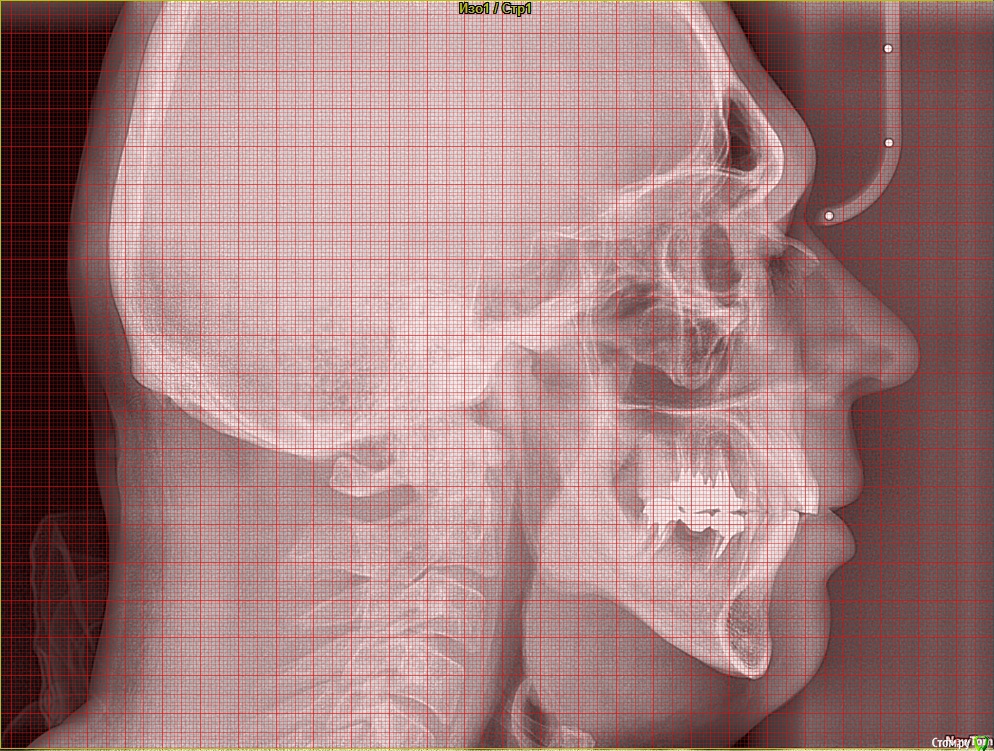

Taurus007 Опубликовано 9 февраля, 2018 Поделиться Опубликовано 9 февраля, 2018 После очных консультаций в разных клиниках (Москва) выяснилось много вариантов, что несколько смущает. Рекомендации и планы лечений такие:1.Удалить 15,16.25,26,37,47 . С учетом ранее удаленных 2х нижних шестерок, поставить 8 имплантов.При необходимости - подсадка костной ткани.2.Удалить 46,47,36,37,16,26, на их место импланты. 15,25 - поменять коронки. Дополнительно: а. Синус-лифтинг в различных комбинациях, либо без него. Мнения разные. б. Высказано мнение, что необходима коррекция прикуса, поскольку если его не трогать, а начать установку имплантов, то нагрузка на них будет чрезмерной, что повлечет рассасывание кости со всеми вытекающими. Сделал ТРГ, пока только снимок, анализ и расчет ТРГ на след. неделе будет готов. Из истории зубов: коронки стоят 9 лет, 35й - 1 год. Ссылки на ТРГ и компьютерную томографию . Сам я изначально склонялся к первому варианту. Без исправления прикуса.Подскажите, как все-таки лучше поступить? Важные вопросы: насколько необходимо исправление прикуса, и нужен ли синус-лифтинг, судя по КТ? Ссылка на комментарий

Taurus007 Опубликовано 13 февраля, 2018 Автор Поделиться Опубликовано 13 февраля, 2018 wladdXОгромное спасибо за скриншоты. Я бы даже близко так не смог) Пришел расчет и анализ ТРГ. Заключение.pdf Ссылка на комментарий

Bier Опубликовано 22 февраля, 2018 Поделиться Опубликовано 22 февраля, 2018 Справа синуслифтинг не потребуется 100%Слева - возможно в области 26 зуба. Для оценки прикуса одного ТРГ мало, надо еще фото моделей. Вам их наверное делали? Ссылка на комментарий